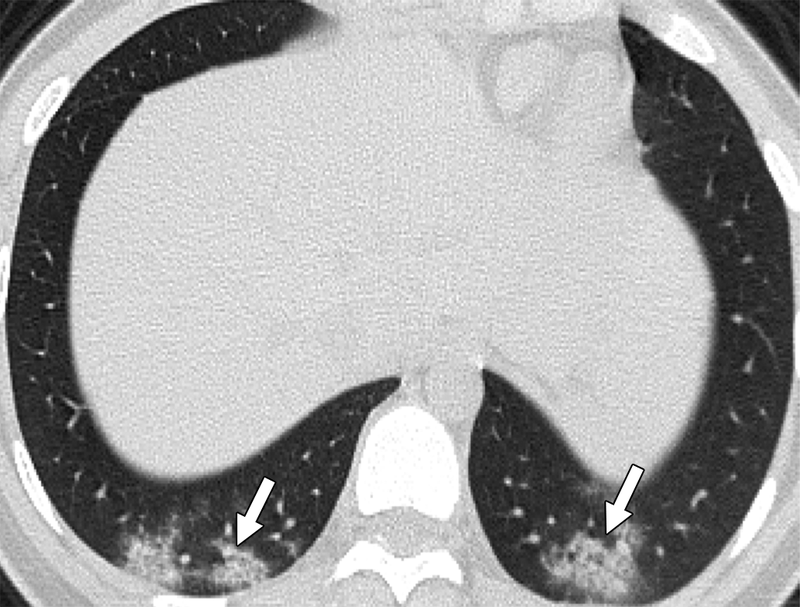

Side-by-side images show lung ultrasound pinpoints same findings as low-dose chest CT.

Submillisievert chest CT scans offer quick and accurate assessment, particularly in patients with symptoms more than 48 hours.